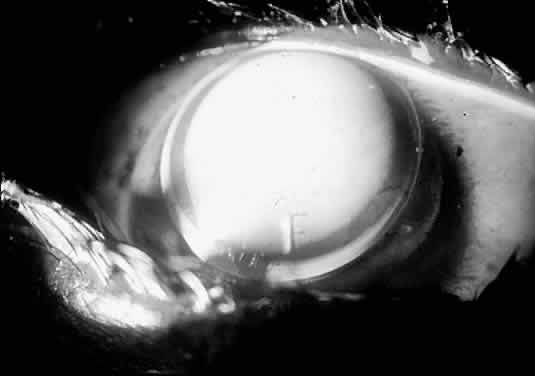

Fig. 19. Well-fitting Soper keratoconus lens. Fluorescein pattern is uniform over the cone.

Because these lenses are fitted strictly from a diagnostic set and calibrated by sagittal depth (Fig. 20), the CPC and diameter of the dispensed lens are taken from the properly fitting diagnostic lens itself. Therefore, the only calculation necessary is the power of the lens. This calculation is performed similarly to the method for standard rigid lens fitting. Note, however, how the CPC is expressed for this type of lens: central curve/peripheral curve, for example, 54.00/45.00 D.

Fig. 20. Sagittal depth for the Soper keratoconus lens diagnostic set. Each lens has a letter engraved on it for identification purposes. The CPC and diameter of the set is varied lens by lens to achieve a near linear sagittal depth relationship.